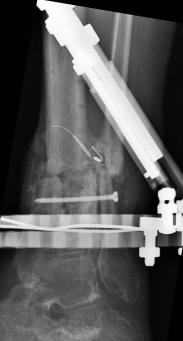

Postoperative (13th) images of left ankle

The image(s) displayed here were created following Liam's 13th surgery which was performed by Dr. Saunders. After a few hiccups getting

the surgery scheduled, Liam spent most of the September 13th afternoon in his 13th surgery. ;-) The surgery lasted about 5 hours and according

to the doctor, it was a good surgery. The 1st photo shows the new frame bracing that holds Liam's ankle together. The next series of photos show

various angles of the ankle and the rods that go from the frame into and through the left ankle. There was some concern that the swelling would

burst and allow for infection. Looks like we are now past that concern. Liam is still on antibiotics to ward of potential infection. The flesh

images show how the skin reacts to having the leg adjusted by the brace. The doctor has had to cut the skin to allow the rods to move freely.